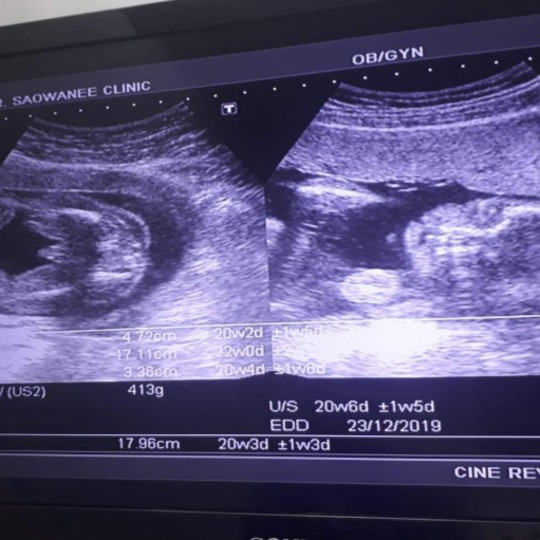

ใบซาวด์

ขอดูใบซาวด์แม่เพศ ชาย หญิง หน่อยค่ะ